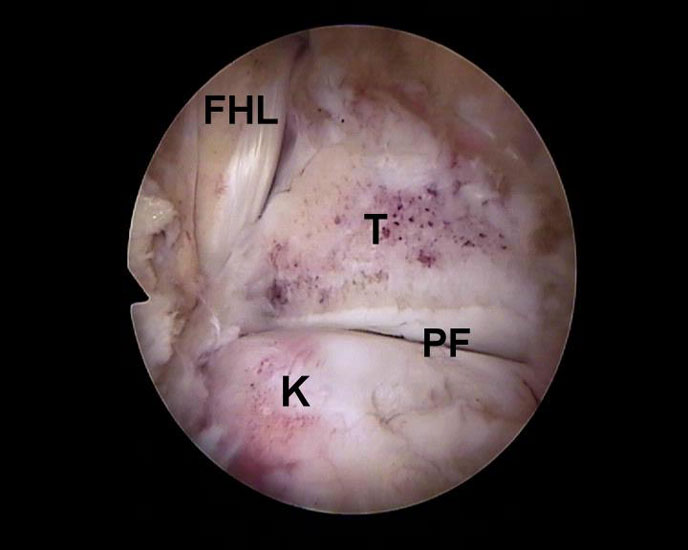

Abbildung Nr. 11-13

Das Os trigonum wird aus dem Weichteilgewebe gelöst und anschließend mit einer Fasszange entfernt. Bei größeren Knochenfragmenten muss ggf. das mediale Arthroskopieportal um wenige Millimeter verlängert werden, um die Extraktion zu ermöglichen. Nach Resektion des Os trigonum ist die posteriore Facette des Subtalargelenks erkennbar (rechte Seite, PF=posteriore Facette, FHL=Flexor hallucis longus-Sehne, T = Talus, K = Kalkaneus, *=Os trigonum).